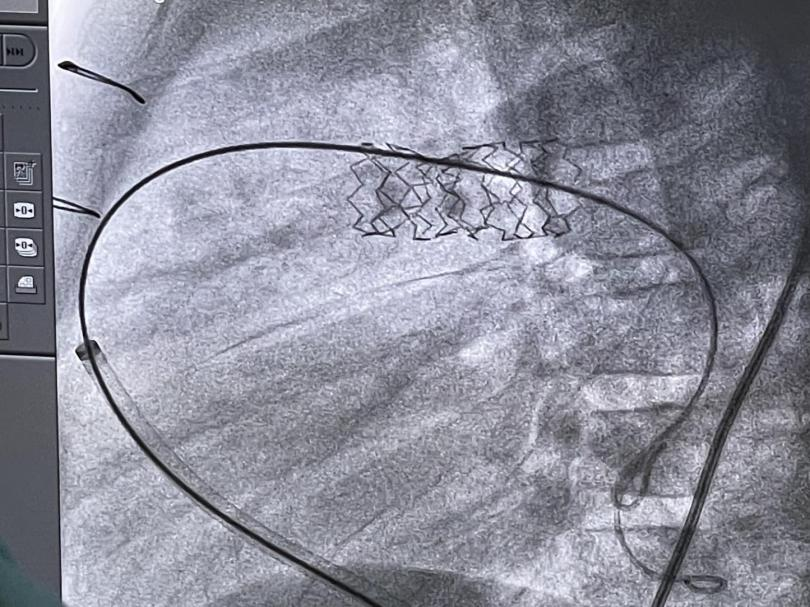

使用BIB双层球囊,将支架扩张至12mm,与患儿正常血管直径相吻合。